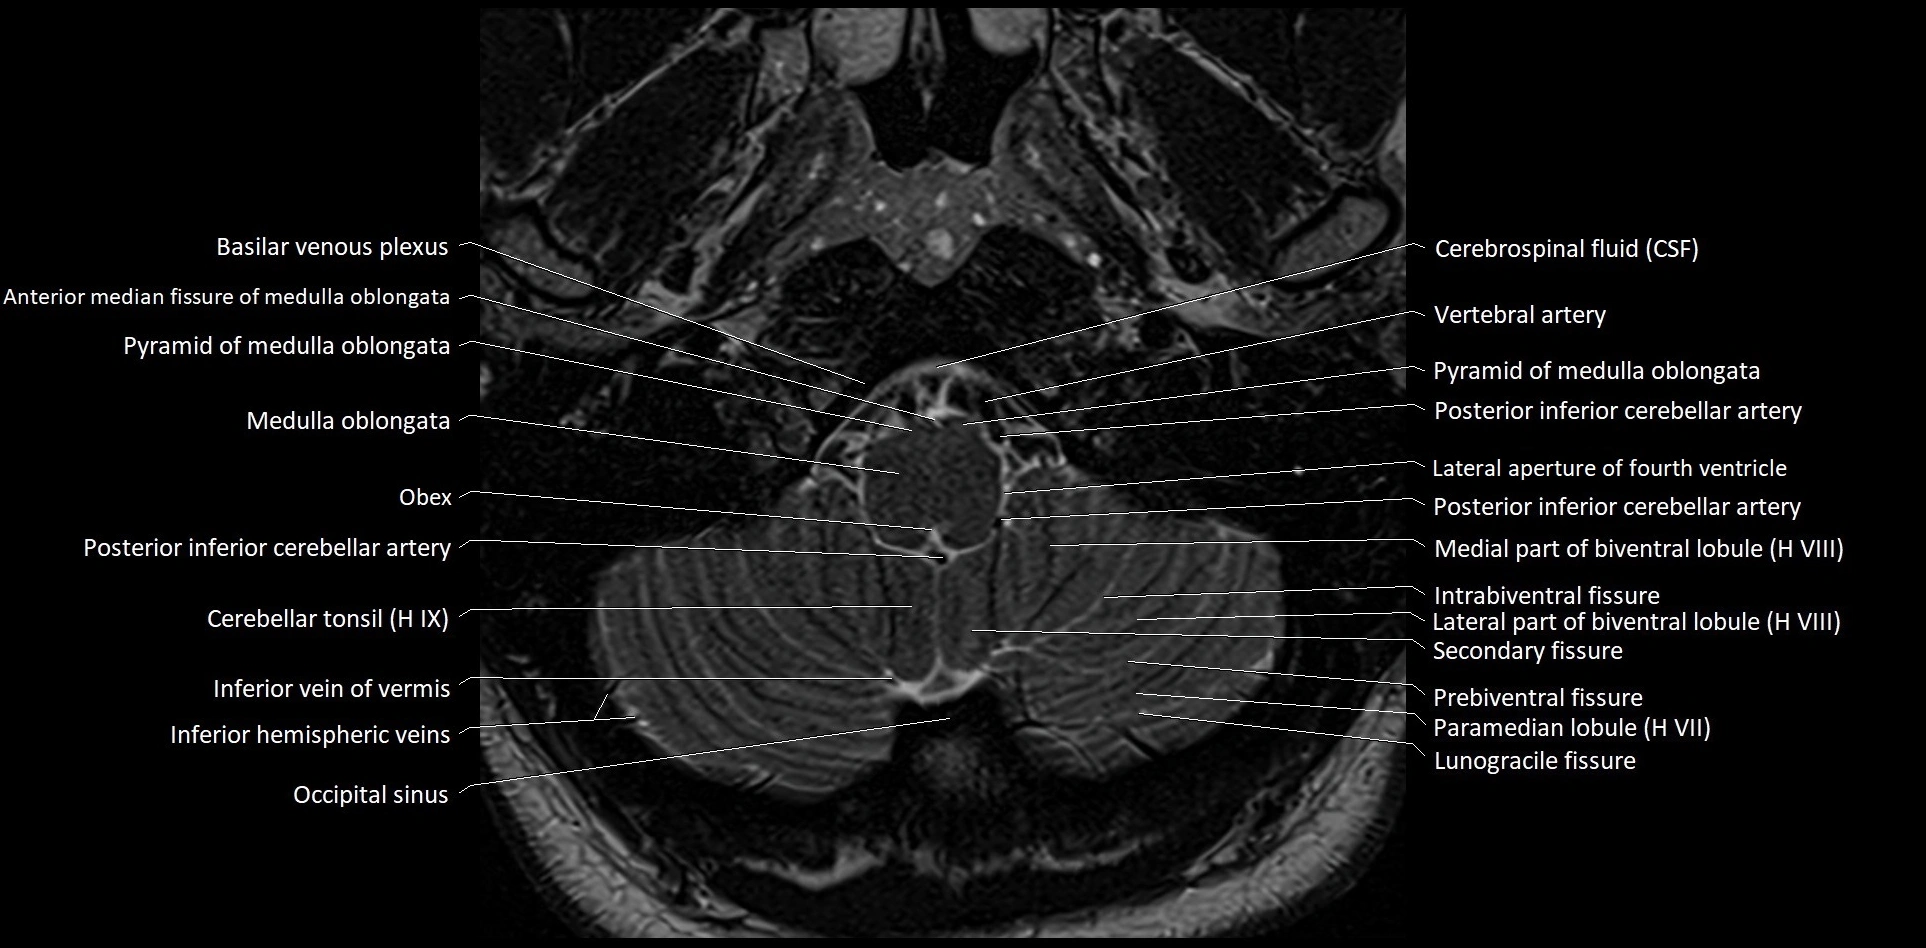

MRI images